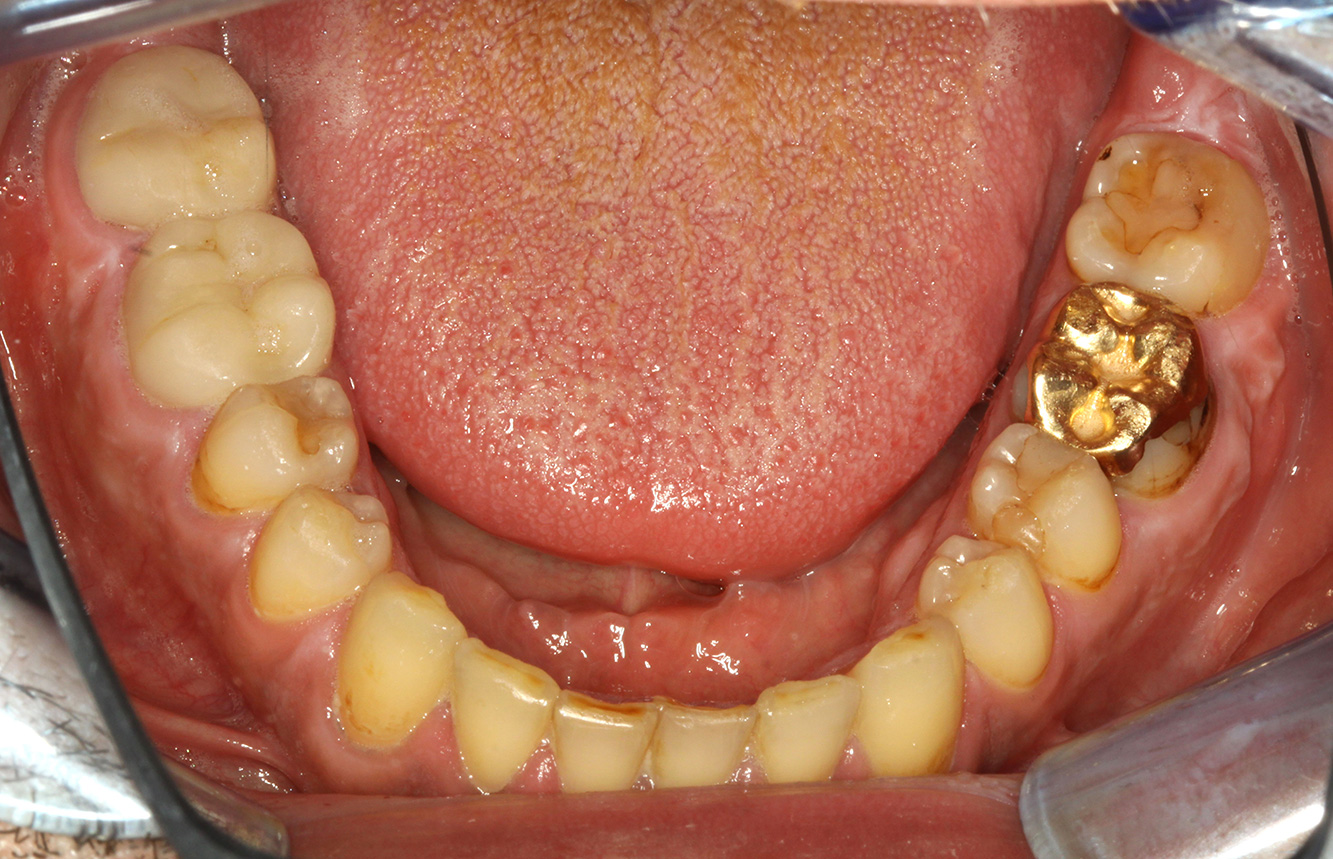

Der Patient ist 39 Jahre mit Z.n. Herzklappenersatz wegen Klappenfehlers und Endokarditis. Als Antikoagulans (Gerinnungshemmer) wird regelmäßig ASS 100 eingenommen. Aus dem Bereich Lebensstil ist die Ernährungsweise als kariesfördernd einzustufen, da mit hoher Regelmäßigkeit zuckerhaltige Lebensmittel sowie sechs bis sieben Mahlzeiten täglich verzehrt werden. Die Mundgesundheit des Patienten zeigt ein mittleres Kariesrisiko mit aktiven Läsionen. Das Parodontitisrisiko ist niedrig, es besteht eine Gingivitis. Es ergeben sich folgende Empfehlungen für die Prophylaxebehandlung.

Für die Prophylaxesitzung lassen sich keine spezifischen Instrumentierungsempfehlungen ableiten. Durch den gezielten Einsatz von Pulverstrahl und rotierend Polieren können Plaque und Verfärbungen an den Restaurationsrändern schonend entfernt und Wiederbesiedlungsnischen für kariogene Bakterien reduziert werden (19).

Zur weiteren Unterstützung der Kariesprävention ist eine Fluoridierung, besonders um der Neuentstehung im Bereich der Restaurationsränder vorzubeugen, und eine Versiegelung der Wurzeloberflächen empfehlenswert. Beide Maßnahmen können die angegebene Temperatursensibilität der Zähne reduzieren.